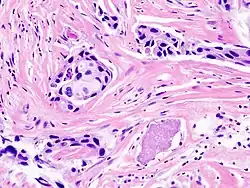

CNB wykonywana z obrazowaniem radiologicznym szybko zyskała popularność już po pierwszych publikacjach Parkera i in. w 1993 r.[19] W tej technice stosuje się igły większego kalibru (rozmiar 14–16 G). Do manualnego wykonania zabiegu służą strzykawki z tłokiem sprężynowym osadzone w specjalnej obudowie. Naciśnięcie spustu zwalnia tłok, wykrawając fragment z miąższu gruczołu. Pobieranie kolejnych próbek wiąże się z każdorazową wymianą igły, co sprzyja lokalnemu krwawieniu[20].

Technika CNB likwiduje wiele niedostatków badania FNAB. Wykorzystując ultrasonografię bądź stereotaksję rozpoznanie cechuje większa precyzja, w szczególności kiedy zmiany mają charakter lity lub mikrozwapnień[13]. Wskaźniki diagnostyczne (czułość, precyzja) osiągają wyższe wartości[17][21], a spójność pobranego wycinka umożliwia ocenę jego architektury. Podane właściwości umożliwiają odróżnienie raka naciekającego od nowotworu in situ[19][21].

Godnym uwagi problemem, którego znaczenie kliniczne rozważano przez pewien czas, była kwestia możliwości rozsiewu nowotworu podczas nakłuwania igłą[22][23]. Im większy kaliber instrumentu, tym łatwiej naruszyć strukturę guza, przypuszczalnie zwiększając stopień zaawansowania zmiany (aparaty VAC wymykają się tej regule z powodu ukierunkowanej siły ssącej)[24]. W literaturze istnieją opisane sporadyczne przypadki miejscowych wznów, które były przypisywane przeprowadzonej uprzednio biopsji[25][26][27]. Systematyczne badania nie potwierdziły tych obaw: zwykle komórki nowotworowe szybko ulegają nekrozie po wyciągnięciu ze swego zwykłego otoczenia[22][28]. Obserwacje te są zgodne z aktualnymi poglądami na patogenezę choroby; rozwój formy inwazyjnej wymaga nabycia kilku kluczowych mutacji, które pomagają przeżyć komórkom w obcym, niesprzyjającym środowisku[29]. Ich przedwczesny transfer musi zatem zakończyć się śmiercią. Samo leczenie wczesnych nowotworów piersi obejmuje też sesje radioterapii, która z założenia ma niszczyć miejsca lokalnych mikroprzerzutów.

Odsetek rozpoznań fałszywie ujemnych mieści się w przedziale od 0–9%[30][4], ze średnią wartością ok. 0,4%[3]. Najczęstszą przyczyną porażki diagnostycznej pozostaje podjęcie próbek spoza sondowanej zmiany.